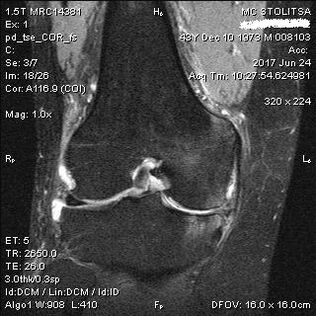

Diagnose und Behandlung von Arthrose des Kniegelenks

Die Diagnose einer Arthrose des Kniegelenks erfolgt in der Praxis eines Rheumatologen oder Orthopäden. Der Arzt untersucht das betroffene Gelenk, tastet es ab, hört sich Beschwerden an und stellt ergänzende Fragen. Er führt verschiedene Tests durch und bittet den Patienten beispielsweise, das Bein zu beugen oder ein paar Schritte zu gehen. Wenn es also notwendig ist, das Krankheitsstadium oder die Art der pathologischen Veränderungen zu klären, wird er Sie zu weiteren Untersuchungen verweisen. Zum Beispiel für Computertomographie oder Röntgen.